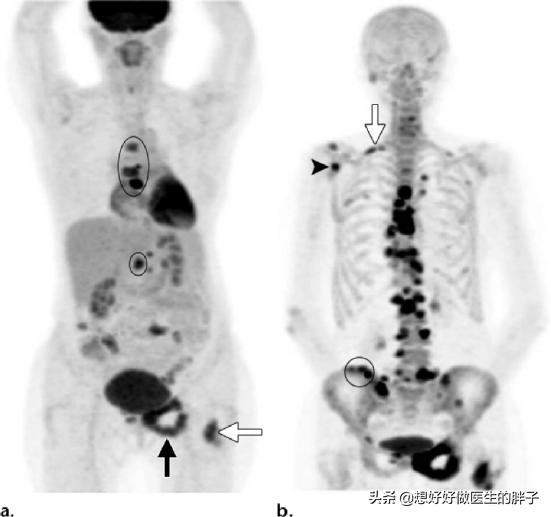

Quel type de douleur doit alerter sur la présence de métastases osseuses ? Les métastases osseuses sont une manifestation fréquente des tumeurs malignes à un stade avancé. La tumeur primaire présente dans d'autres parties du corps se métastase dans les os par les voies sanguines et lymphatiques, formant ainsi des métastases osseuses. Les métastases osseuses signifient que le tissu osseux normal a été détruit et remplacé par du tissu tumoral. Les métastases osseuses peuvent être classées en trois types selon la spécificité de la lésion : le type ostéolytique, le type ostéogénique et le type mixte. Les sites courants de métastases osseuses sont l'os de la diaphyse moyenne (colonne vertébrale et bassin), les côtes et la métaphyse inférieure, l'os de la diaphyse moyenne étant le plus courant, ce qui est lié aux caractéristiques de l'apport sanguin dans cette zone. Comme le montre le cercle ci-dessous, les métastases osseuses sont multiples et la colonne vertébrale est en mauvais état.

Pour les patients sans antécédents de cancer, et si la famille est financièrement aisée, il est recommandé de réaliser un examen PET-CT pour rechercher des lésions cancéreuses suspectes sur l'ensemble du corps, ce qui permet de déterminer de manière adéquate la présence de lésions tumorales, leur degré d'évolution et le type de foyers métastatiques qu'elles présentent.

En cas d'antécédents de cancer et si le degré de malignité est jugé élevé à l'époque, il est possible de déterminer la présence de métastases osseuses par une scintigraphie osseuse du corps entier. Parallèlement, le degré de destruction osseuse au niveau du site de la métastase peut être clarifié par un examen par résonance magnétique.